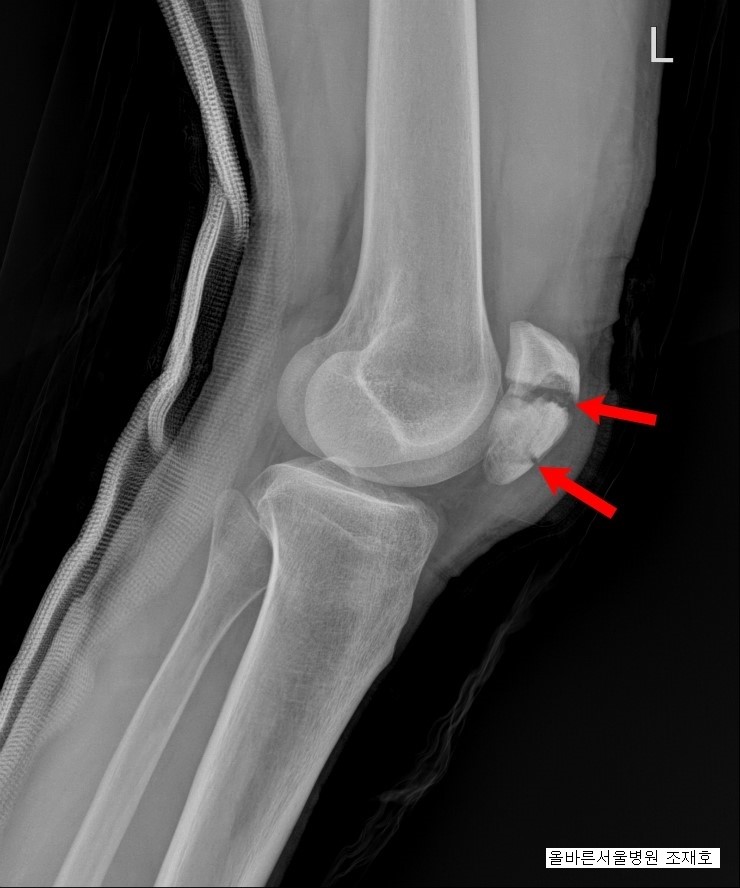

1) 슬개골 골절(슬개골 골절)이란?

슬개골의 구조는 단순하지 않습니다. 대퇴사두근이라는 큰 근육이 붙어 있기 때문에 슬개골에 문제가 생기면 안정적으로 걸을 수 없게 되고 각종 질환에 걸릴 수 있으며 나중에 수술을 하더라도 후유증이 생기기 마련이다. . 그 증상은 다양하지만 대표적인 것이 운동범위의 제한과 통증이며, 골절 시 주사나 석고주사 등은 보행 장애를 유발할 수 있어 고령일수록 이런 현상이 발생하기 쉽다. 골절의 증상이 나타난 후에는 물리치료와 도수치료를 통한 관리가 필요합니다.

2) 슬개골 골절 후유증(슬개골 골절)

수술 후 혈전이 뇌혈관을 이탈시켜 막을 수 있는데 이는 불가피한 부작용은 아니지만 일단 발생하면 뇌경색의 위험이 있기 때문에 운동은 혈전 예방을 위해 필요한 조치이다. 이 운동을 하는 방법은 매우 간단합니다. 누워서 발목을 위아래로 흔들기만 하면 됩니다. 또한 깁스의 수명으로 인해 장시간 누워있으면 근육손실이 가속화되기 때문에 근력을 유지하기 위한 운동이 필요합니다. 조심하고 일어나서 천천히 움직이는 습관을 기르십시오.